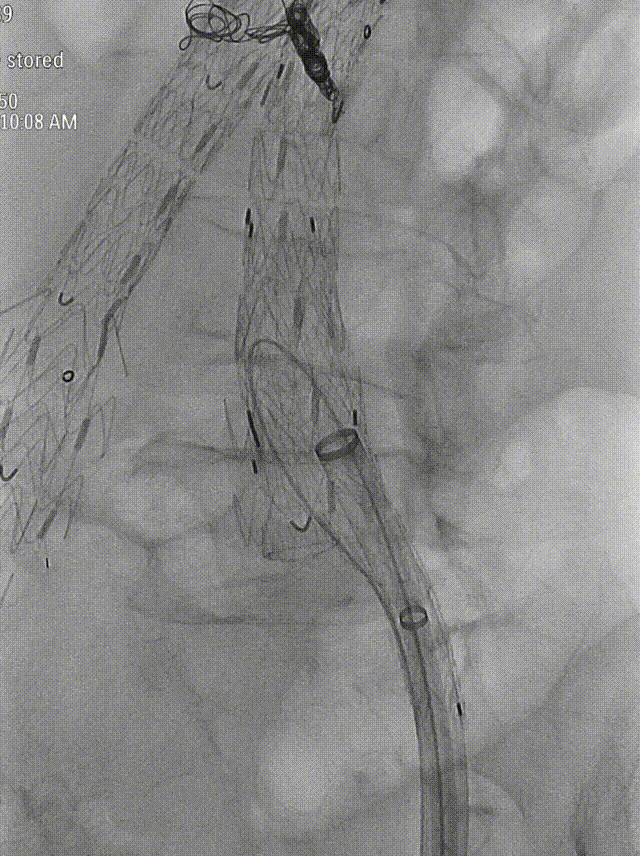

造影:支架定位准确,形态良好,未见明显受压。双侧肾动脉显影同前,原主动脉及双侧髂动脉血流通畅,至延迟相瘤腔内未见明显内漏,左侧髂内动脉显影可。

gore医疗怎么样「漫腹精论」独具匠心 推陈出新——同侧IBE支架内翻山重建髂内动脉治疗EVAR术后内漏病例报道_https://www.jmylbn.com_新闻资讯_第21张

术后造影

gore医疗怎么样「漫腹精论」独具匠心 推陈出新——同侧IBE支架内翻山重建髂内动脉治疗EVAR术后内漏病例报道_https://www.jmylbn.com_新闻资讯_第22张

术后髂动脉造影